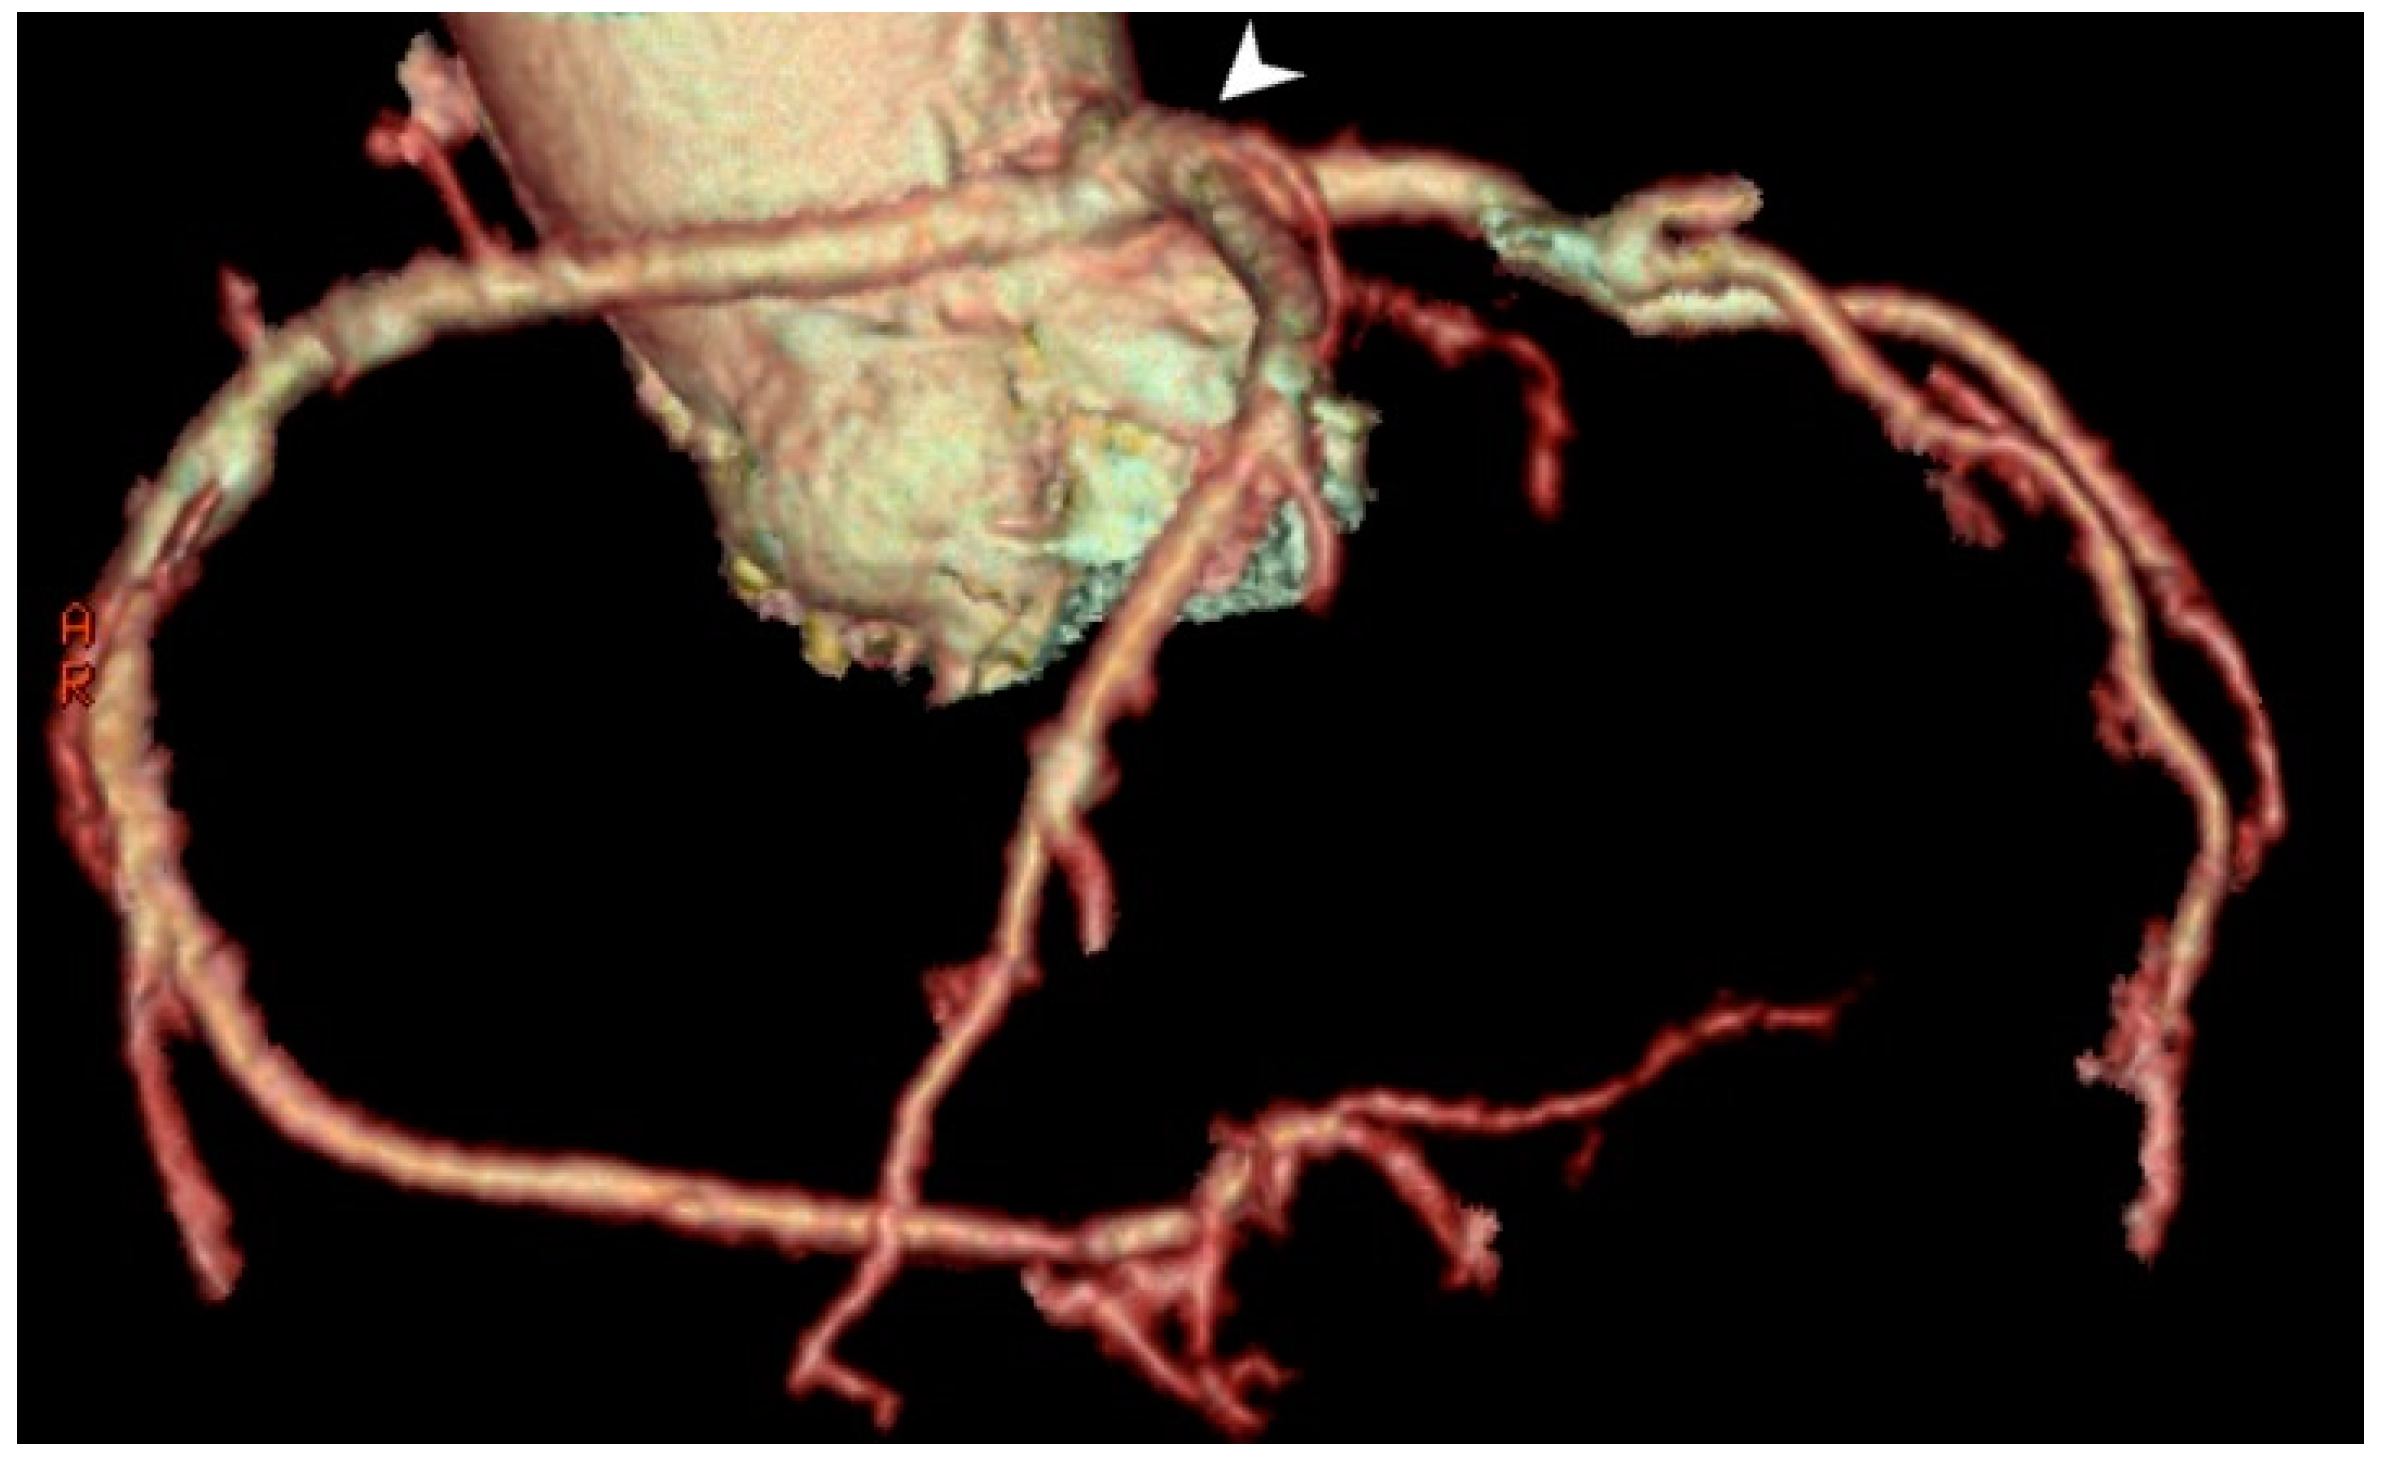

The anomalous origin of the coronary arteries is mostly an asymptomatic anomaly, with the exception of some rare cases when angina, syncope, heart failure, and sudden death may occur. The anomalous origin of LCX from the right coronary sinus is a prevalent congenital coronary variation (Figure 2a,b), with a documented prevalence of 0.18–0.67% in the literature [19]. It is typically a benign medical condition, but, in rare instances, individuals may experience atypical chest pain and discomfort [20].

White and Edwards first described an aberrant origin of the RCA in 1948 [21]. The anomalous origin of the RCA from the left sinus of Valsalva (Figure 2c,d) is a rare condition reported in 0.43% of patients undergoing MDCT coronary angiography [22], occurring more often in Hispanic individuals (0.25% of cases). This condition is usually asymptomatic but can be accompanied by anginal complaints, usually during exertion or rhythm disturbances [23].

Figure 2. Patients with aberrant origin of the coronary arteries. (a) Volume-rendered (VR) MDCT image of posterior view of the LCX arising from the right sinus of Valsalva (white arrow head), with its retrobulbar course (white arrow). (b) MDCT planar (axial) view of the LCX arising from the right sinus of Valsalva (red arrow head), with its retrobulbar course, moving between the aortic root and left atrium (red arrow). (c,d) MDCT image of posterior view of the single ostia and RCA arising from the left sinus of Valsalva (arrow in (c)), with retrobulbar position and further regular course (arrow head in (d)). With the noted retrobulbar course, these anomalies may occasionally lead to ischemia, especially if the vessel is compressed between great vessels, warranting further evaluation.